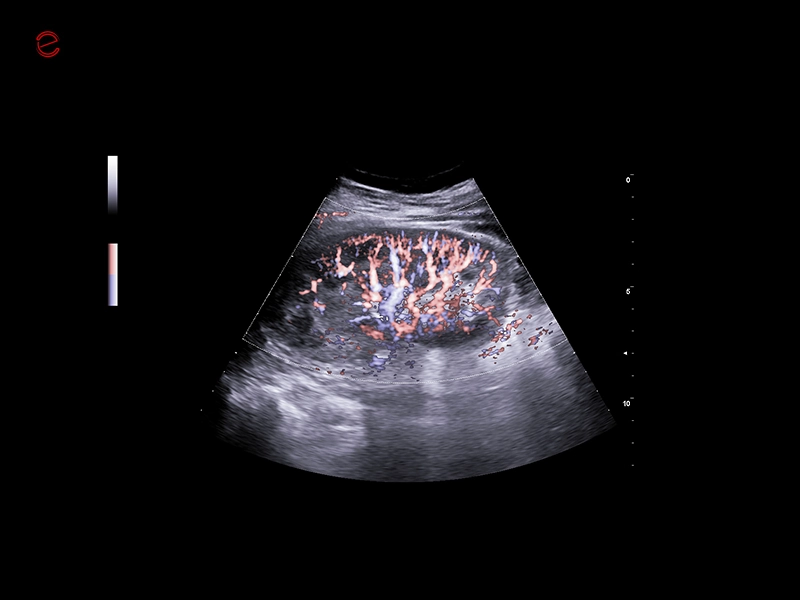

MyLab™9 Platform - Hemodynamics analysis using microV on kidney

MyLab™9 Platform - Hemodynamics analysis using microV on kidney